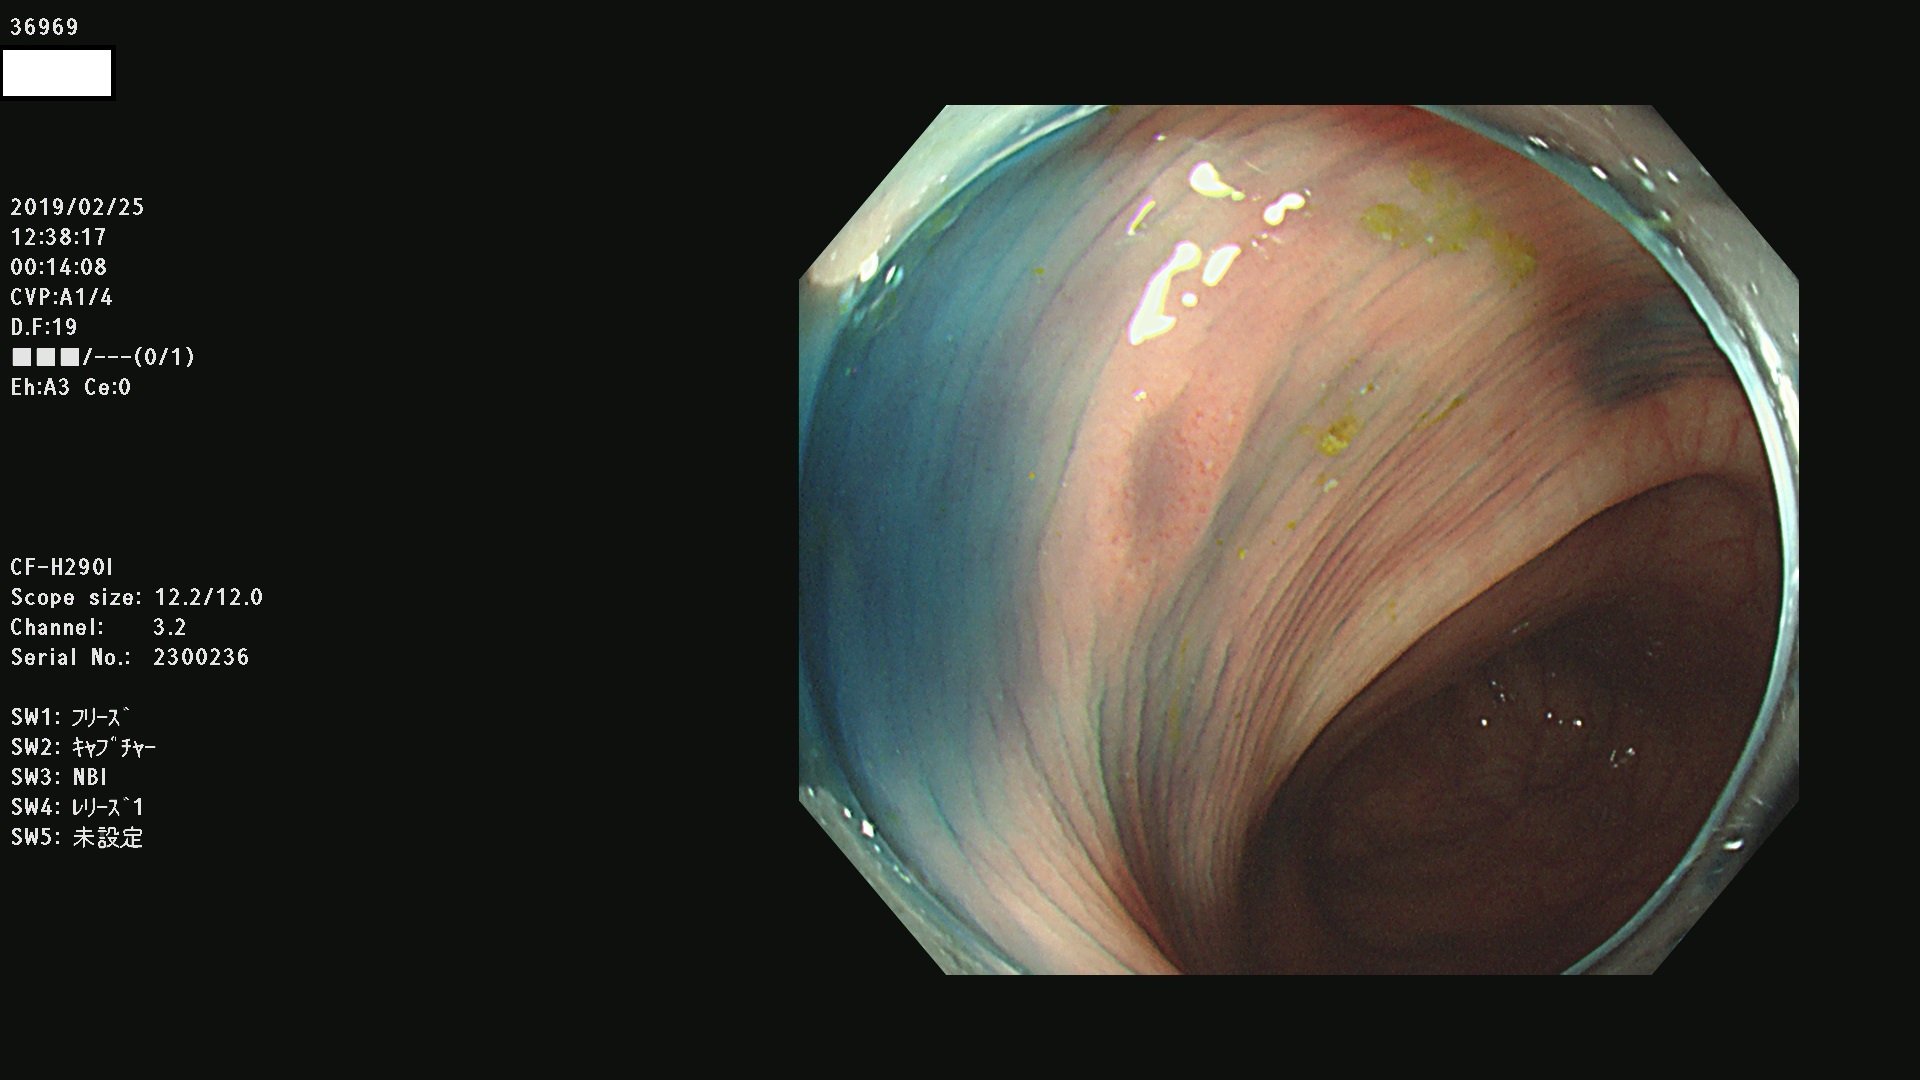

腺腫発見率 67 % (カルテ番号 36900〜36999の100名の方の検査結果で集計)大腸癌検診最新情報

以下のカルテ番号の方に腺腫(Adenoma,Group3〜5)が見つかりました(集計法)

36900 36901 36903 36904 36905 36908 36909 36910 36911 36913 36914 36915 36916 36917 36918 36919 36920 36923 36924 36925 36927 36928 36930 36931(SSAPのみ) 36933 36935 36936 36937 36941 36943 36944 36945 36946 36949 36951 36953 36954 36955 36957 36963 36965 36966 36967 36968 36969 36970 36974 36975 36976 36977 36978 36979 36980 36981 36983 36984 36986 36987 36988 36989 36990 36991 36993 36994 36996 36998 36999

発見困難で危険性の高い平坦型病変(上記100名より抽出) ![]()